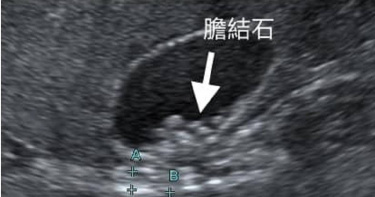

她胃脹吃藥治不好!不到2年暴長8顆「膽結石」 醫示警「這類人」要小心

一名50多歲患者半年來「胃脹」情況頻繁,只要晚餐多吃一些,半夜就會出現胃痛,吃藥也沒有任何改善。之後她一照超音波才發現膽囊「多了7、8顆膽結石」。對此,胃腸肝膽科醫師錢政弘指出,通常膽結石要數年才會形成,但患者不到2年就增長這麼多膽結石,「肥胖就是其中一個危險因子,特別是胖在肚子就容易有脂肪肝和膽結石。」錢政弘醫師近日在臉書粉專分享,「最近我幫一位50多歲的女性病患做腹部超音波,她這半年來胃脹得很頻繁,晚餐吃多一點半夜就會胃痛,吃了半年的胃藥都沒有改善,門診醫師決定幫她排胃鏡和超音波檢查。」結果超音波一照才發現,病人的膽囊多了7、8顆的膽結石,加起來有2至3公分。錢政弘表示,病患過去並沒有膽結石的紀錄,也經歷多次超音波檢查,而上次檢查已是一年半前,當時確實沒有膽結石,「一般膽結石要數年才會形成,怎麼才一年半的時間就長這麼多顆呢?」錢政弘因此進一步詢問對方,體重是否有任何異狀,患者則說自己這2年胖了4公斤,因為少出門,每天在家吃下午茶,喝咖啡配甜點、蛋糕和餅乾等,「應該是甜食吃太多才變胖。」錢政弘由此判斷,病人肚子不舒服並非是胃脹,而是膽結石所引發的疼痛,他也建議患者,接下來應避免吃高油脂的食物,包括蛋糕等,疼痛才不會復發。他提醒,「喝咖啡是可以減少膽結石,不過如果是加糖又配甜點可就沒效了!」錢政弘也示警,「肥胖是膽結石的危險因子,尤其是中廣型肥胖的人特別容易有膽結石,我和同事在基隆和新北市的社區流行病學調查發現,『腰圍和身高比大於0.5』的人,得到膽結石的風險多1.65倍。」例如身高160公分的人,腰圍如果大於80公分,就屬於中廣型肥胖(胖在肚子),代表腹部的內臟脂肪太多,特別容易有脂肪肝和膽結石。錢政弘補充,一般提到「腰圍過粗」是指男性大於90公分/33.5吋,女性大於80公分/31.5吋;但有些人高、有的人矮;因此另一個新的算法是不分男女將「身高÷2」當作腰圍標準,如:某人身高160公分÷2=80公分,腰圍就應小於80公分,超過的話就屬腰圍過粗,屬於中廣型肥胖。